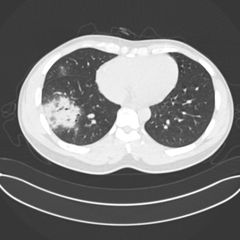

| Colorized scanning electron micrograph of an apoptotic cell (purple) infected with SARS-COV-2 virus particles... |